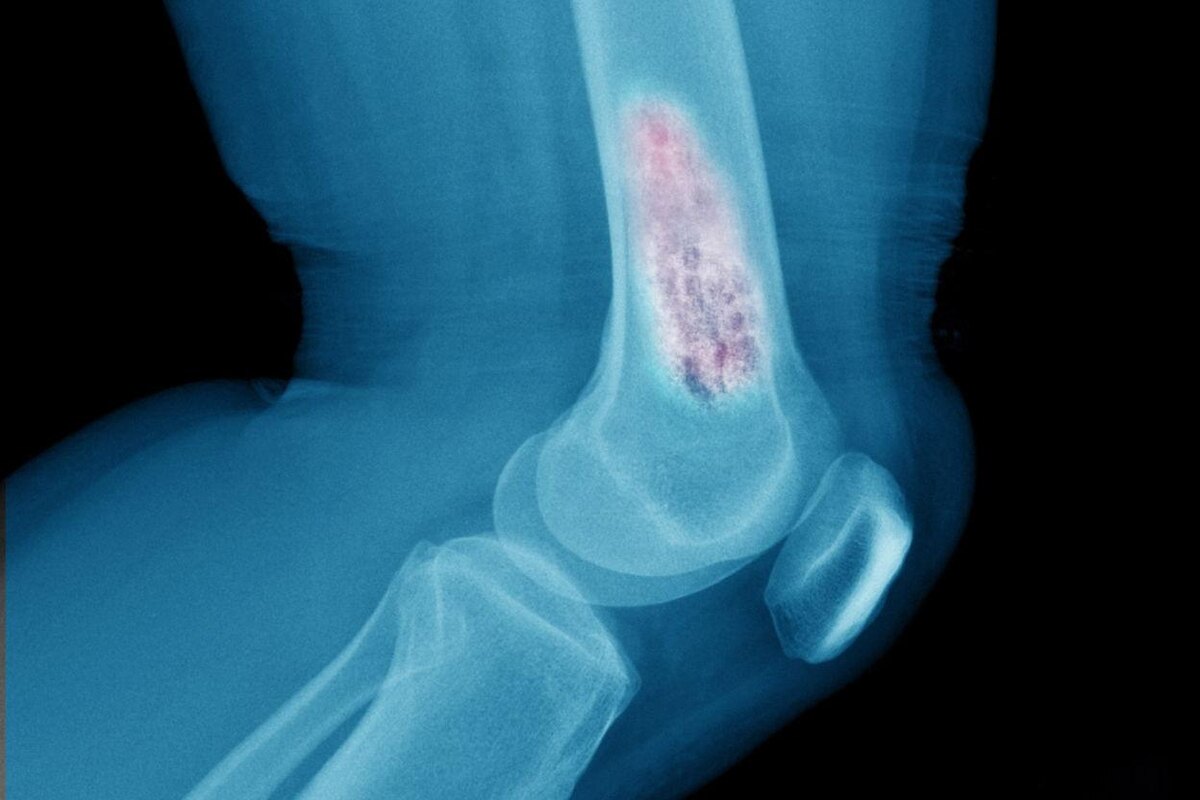

• Остеосаркома — самый часто встречающийся вид опухоли, которая формируется из мезенхимальных клеток (клеток-предшественников костной, хрящевой, мышечной ткани) в участке кости, который твердеет по мере роста. Это могут быть трубчатые кости (зоны около суставов), осевые кости скелета, челюстно-лицевые кости.

• Рентген — снимки пораженного участка позволяют определить нарушения структуры и повреждения кости.